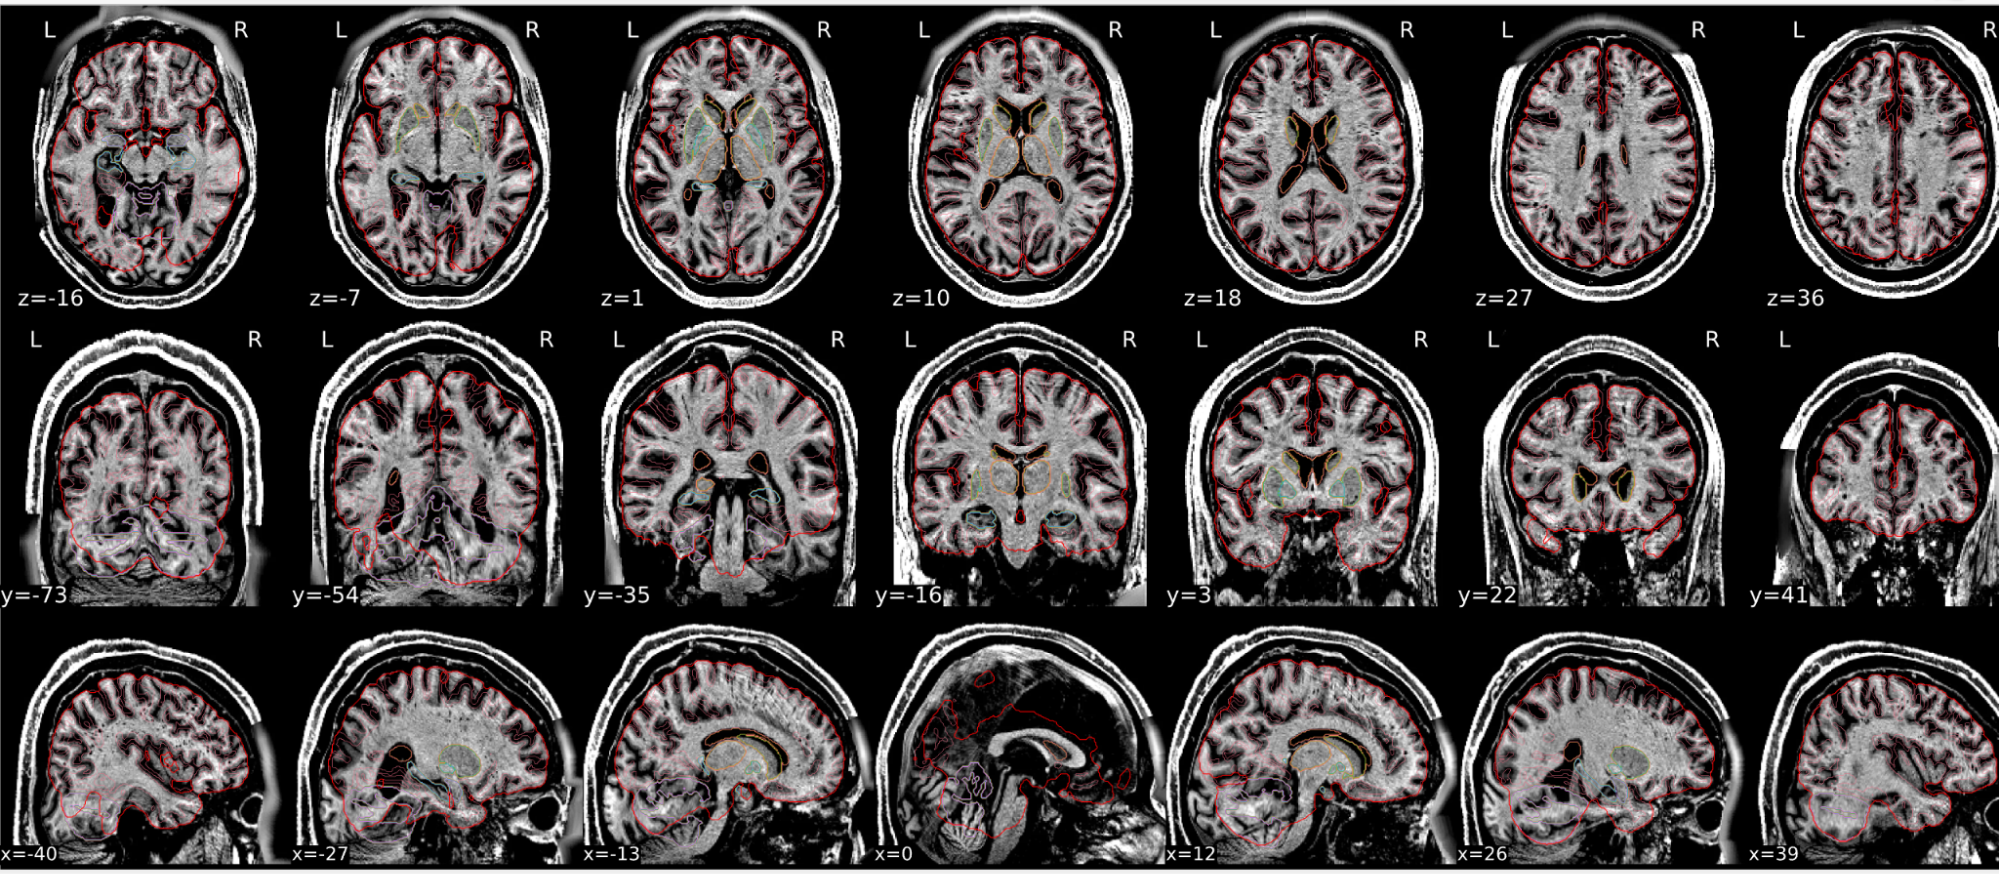

T1w skull stripping

Skull stripping is the process separating the brain (cortex and cerebellum) from the skull. The red line follows the outline of the brain and it separates it from the skull.

Example of a good subject

- There are no skull stripping errors, such as portions of the brain missing, or too much of the skull retained

- The red line follows the outline of the brain

Example of a bad subject

- There are skull stripping errors, such as portions of the brain missing, or too much of the skull retained

- NOTE: check all the images (slices) in the report. If only one image (slice) looks problematic, it is possible that the subject is okay and it is just a visual issue in that particular screenshot

Summary

| Good | Bad |

|---|---|

| The brain is fully inside the red line | Structures like the cranium or the eyes are inside the red line |

| No important brain structures are outside of the red line red line follows the natural outline of the brain | Important brain structures are missing inside of the red line |

-> if only one slice is problematic, it could be an issue related to the visual depiction of the data instead of an issue related to the test subject